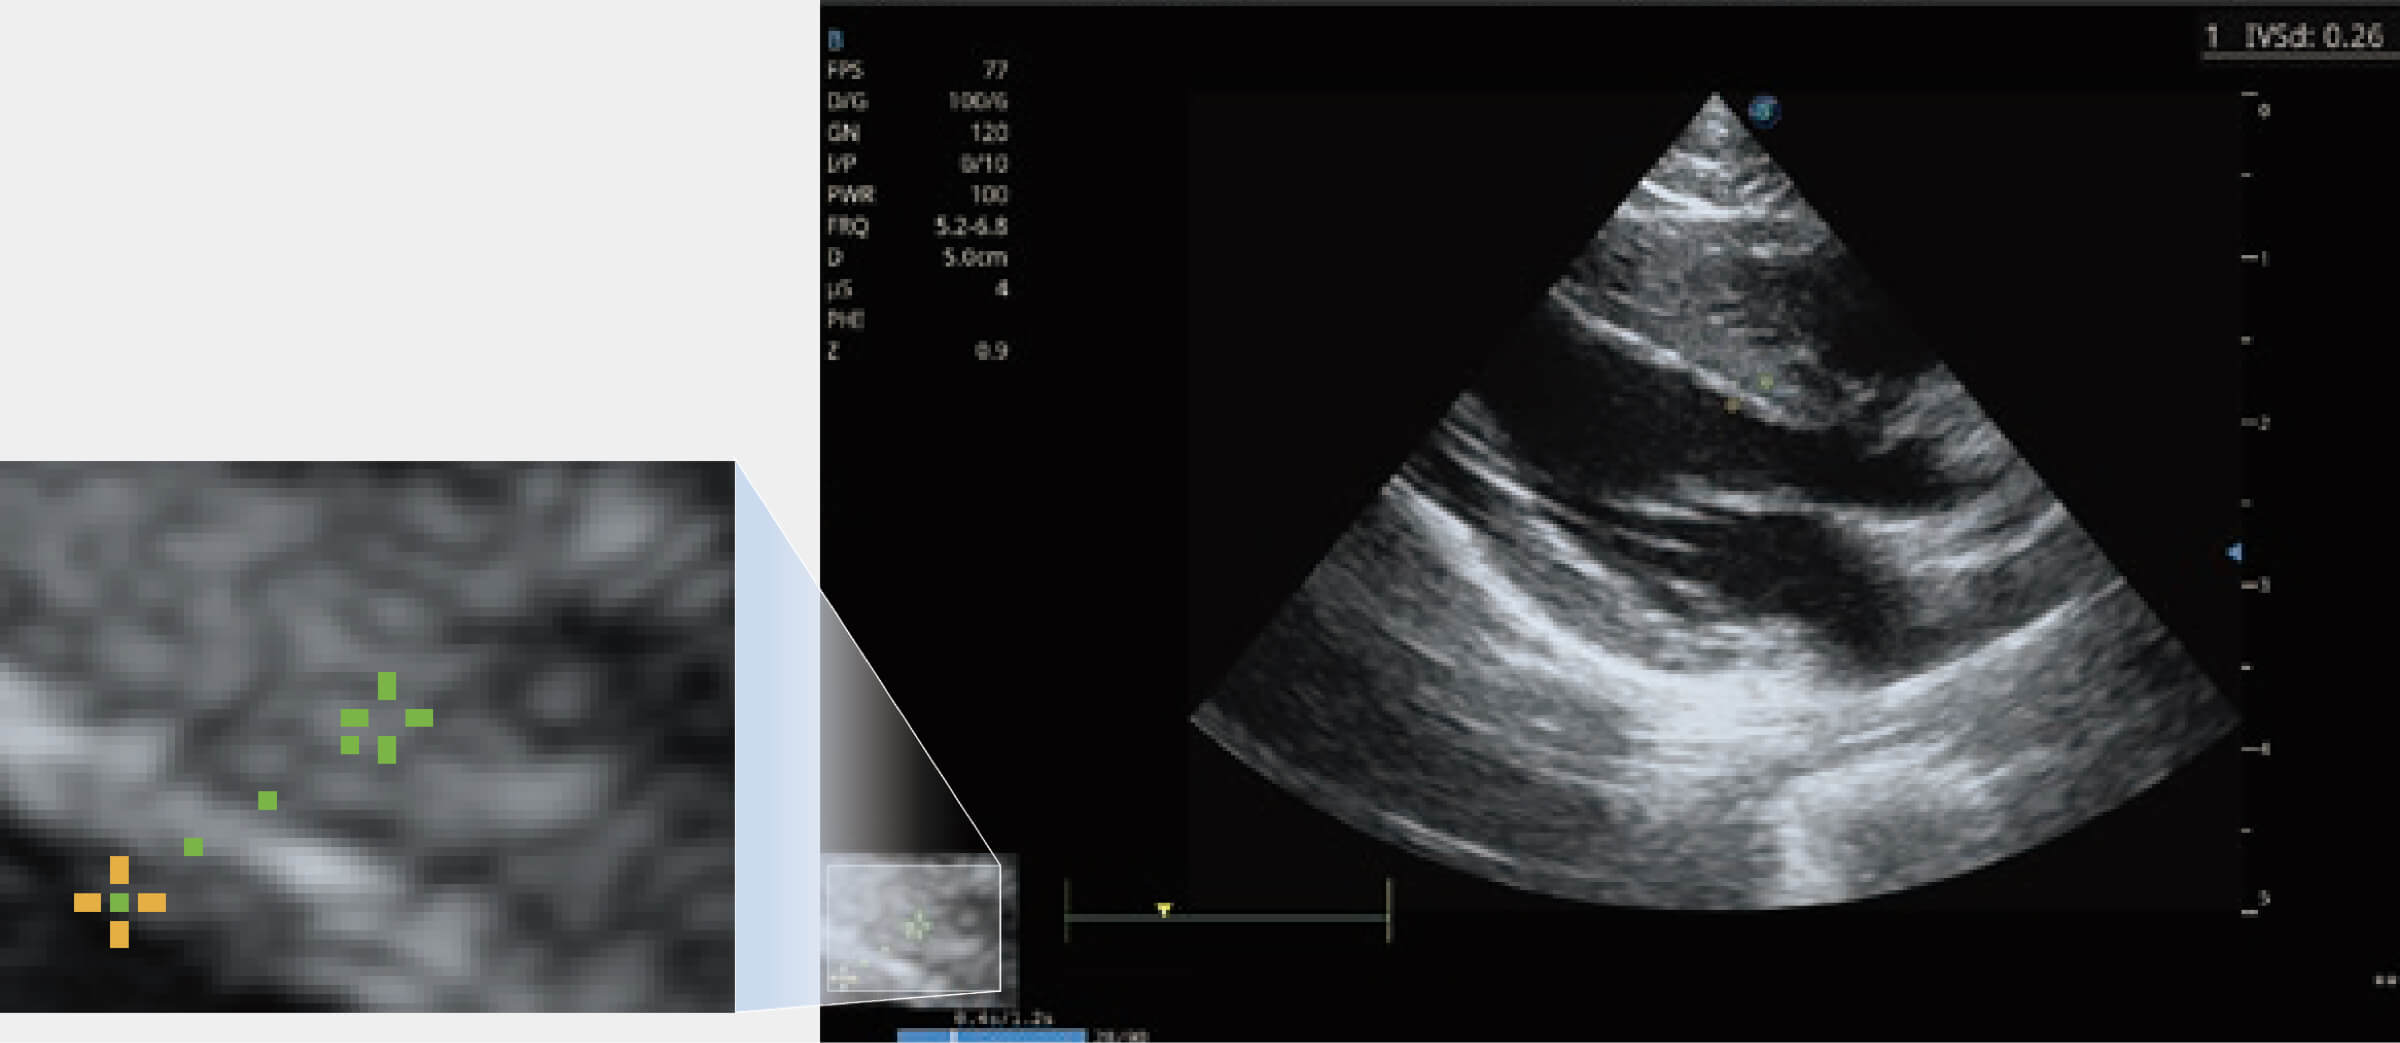

通過360度任意調(diào)節(jié)3條M型取樣線,在同一心動周期上觀察心臟不同位置的運動曲線,得到準確的心功能測量數(shù)據(jù),有效評估心肌運動及左心室功能。